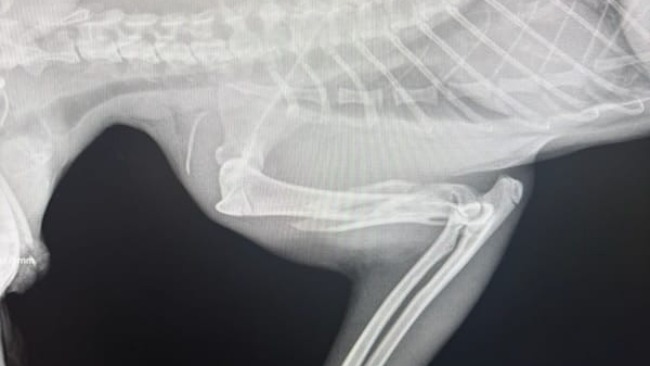

Lucjuszek jest po operacji łapki i po operacji szczęki, w której konieczna była częściowa amputacja. Miednica i ogonek są złamane i na ten moment leczone zachowawczo. To nie jest prosta rekonwalescencja. Dziś znów trafił do kliniki z powodu silnego bólu. Sytuacja jest dynamiczna, reagujemy na bieżąco.